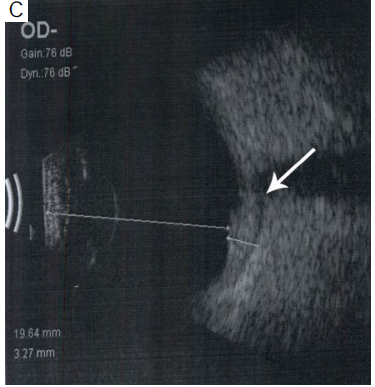

Figure 1 (A) At baseline color fundus photograph shows

hyperemic disc with retinal edema; (B) spectral domain optical

coherence tomography (SD-OCT) shows choroidal elevation with

choroidal folds along with subretinal fluid; (C) ultrasonography

shows choroidal thickening with presence of fluid (arrow) (T sign)

suggestive of posterior scleritis.